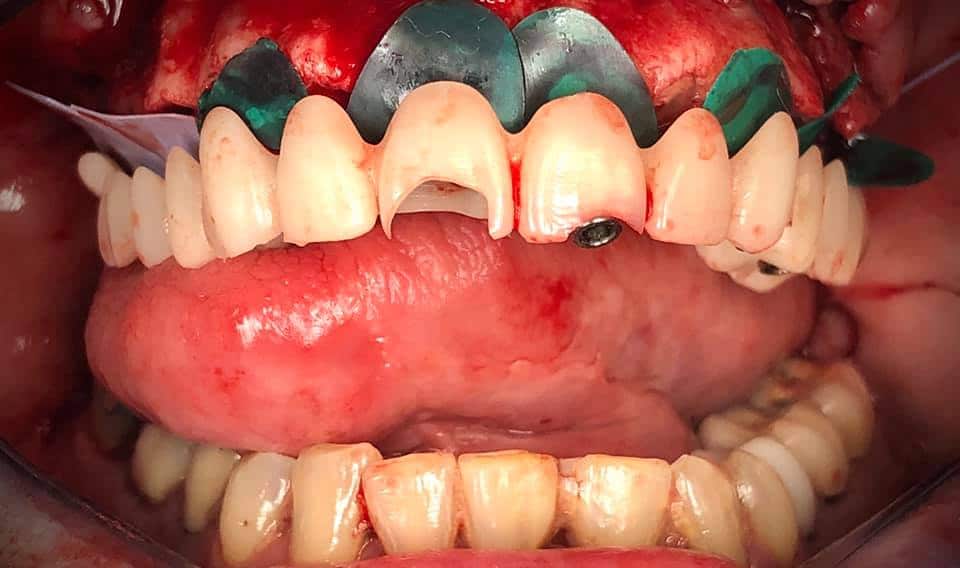

Below is a case of full arch same day temporization using the socket shield , root submergence and pontic shield techniques to preserve the site architecture . Neodent GM implants were placed in a guided fashion and same day temporization was performed using a milled PMMA.

The final bridge was constructed in monlithic zirconia.

-Immediate load temp upper